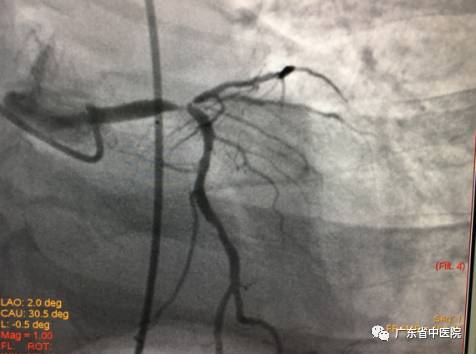

当冠脉造影结果出来后,大家都倒吸了一口冷气:患者是极高危的“左主干”并“前三叉病变”、右冠“慢性完全闭塞病变”。三条冠脉都是重度病变,而且在最重要的冠状动脉左主干末端、前降支开口、回旋支开口都是99%狭窄。稍有不慎,患者随时可能在台上猝死!

造影刚刚结束,患者便又再次出现了室颤。在同家属简单沟通病情后,一场与死神争夺生命的战斗开始了。在IABP辅助下,不到10分钟,旋支支架到位、植入,前降支球囊进行CRUSH操作。正在此时,患者心脏突然停止了跳动!吕主任处乱不惊,马上安排一组人员进行心肺复苏,同时继续操作器械。在体外人工心脏按压的辅助下,成功将最后一枚支架植入,完成血管重建。患者恢复自主心律后,反复出现室速、室颤。这是心肌梗死并发症之一,死亡率极高的“交感电风暴”!团队立即给予电除颤和积极的药物治疗,并派专人24小时守护,以便随时进行心肺复苏。室速、室颤一轮接一轮,经过30余次的除颤、复苏,“风暴”总算过去。病人心律逐渐平稳下来,病情稳定。出院前复查心脏彩超提示左室射血分数已经回升至53%。当病人救治情况反馈回至当地医院后,他们对省中医院的救治水平给予了充分认可和高度赞扬,认为“这样的病人都能救过来,真是厉害!”

分叉病变手术前后造影